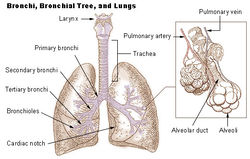

Stavba plic

Každá plíce má zhruba trojúhelníkovitý tvar, levá plíce je menší než pravá. Plicní základna (basis) se dotýká hlavního dýchacího svalu savců, bránice. Plicní hrot (apex) směřuje směrem k hlavě. V plicní brance (hilus) do plíce vstupuje prudůška (bronchus), plicní žíly a plicní tepna, mízní žíly a nervy. Na vnitřní ploše plic jsou otisky orgánů středohrudí, hlavně srdce. Plíce jsou rozčleněné na laloky, u člověka má pravá plíce laloky tři, menší levá má dva. Třetí lalok pravé plíce, lalok přídatný (lobus accessorius) se vsouvá do prostoru mezi velkými žílami a srdcem, u člověka má jazýčkovitý tvar, proto se mu také říká lingula, jazýček. V průměrných plicích se udrží okolo 3 litrů vzduchu.[1] Každý lalok je dále rozdělen vazivovými přepážkami, které vycházejí z poplicnice, na bronchopulmonální segmenty. Každý segment má vlastní přívod vzduchu i krvení. Segmenty jsou dále rozděleny na lalůčky, aciny, které mají pyramidový tvar. Základna acinu je na povrchu plíce, hrot směřuje k plicní brance. Vnitřek plic se skládá z rozvětvujících se prudůšek, tedy dolních cest dýchacích, a dýchacího oddílu, části, kde dochází k výměně plynů. Prudůška, která vstupuje do plic plicní brankou, se 25krát větví (u člověka). Tvoří tak prudůškový strom (arbor bronchalis) Hlavní prudůška (bronchus principalis) → lalokové prudůšky (bronchi lobares) → segmentální prudůšky (bronchi segmentales) → subsegmentální prudůšky → terminální prudůšky V průběhu větvení se mění stavba stěny prudůšek, hlavní prudůška má podobnou stavbu stěny jako prudůšnice, je tvořena chrupavkou, s každým dalším větvením chrupavky ubývá a relativně přibývá hladké svaloviny. Sliznice je pokrytá řasinkovým epitelem, řasinky kmitají směrem ven a pomáhají odstraňovat nečistoty. V průběhu větvení časem zmizí i hladká svalovina, stěna je tvořena jen tenkou sliznicí, s epitelem s řasinkovými buňkami, malým množstvím pohárkových buněk a buňkami Clarovými, které produkují sufraktant, látku, která snižuje povrchové napětí a brání tak kolapsu prudůšky. Jedna terminální prudůška ventiluje jeden plicní lalůček. V něm se větví na prudůšinky (bronchioli), které už patří k dýchacímu oddílu plic. Průdušinky se několikrát rozvětví, až na respirační prudůšinky (bronchioli respiratorii). Tyto prudůšinky ústí do plicních sklípků, alveolů. Každý respirační bronchiolus zásobuje vzduchem asi 200 alveolů.

Plicní sklípky

Alveoly (neboli plicní sklípky) jsou tenkostěnné váčky, ve kterých probíhá difúze dýchacích plynů. Jejich stěna je tvořena pouze jednou vrstvou extrémně tenkých buněk, pneumocytů I. typu. Bazální membrána, na kterou pneumocyty nasedají, přechází ve stěnu okolních kapilár, aby mohly plyny volně přecházet. Alveolární membrána je tlustá jen asi 1 μm. Kromě pneumocytů I. typu jsou ve stěně alveolů i tlustší pneumocyty II. typu, které stejně jako Clarovy buňky průdušek produkují surfaktant (= látka pokrývající vnitřek plicních sklípků, která snižuje povrchového napětí a brání tak smrštění sklípků a následnému kolapsu plic), a makrofágy, tzv. prašné buňky, které fagocytují prach a jiné cizí částice v alveolu. Dohromady v obou plicích je přes 300 miliónů plicních sklípků a jejich celkový povrch je 40 - 100 m2.